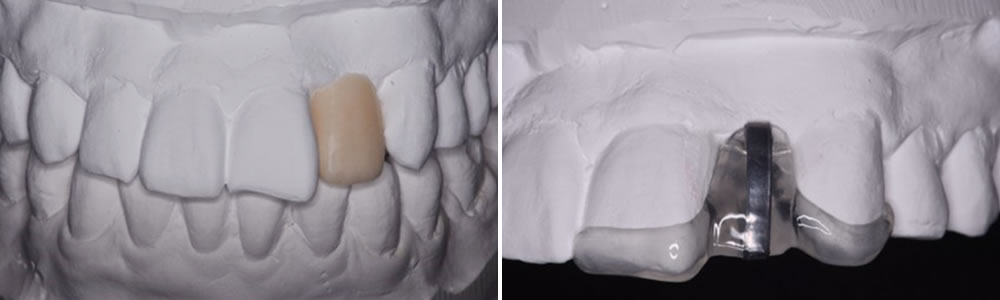

模型でのシュミレーション

模型上にてワックスアップ(シュミレーション)を行い、審美性・咬合の確認、そして埋入位置の診断を行います。 診断用ステントを装着し、CTを撮影してインプラントの埋入位置に問題がないかを確認します。